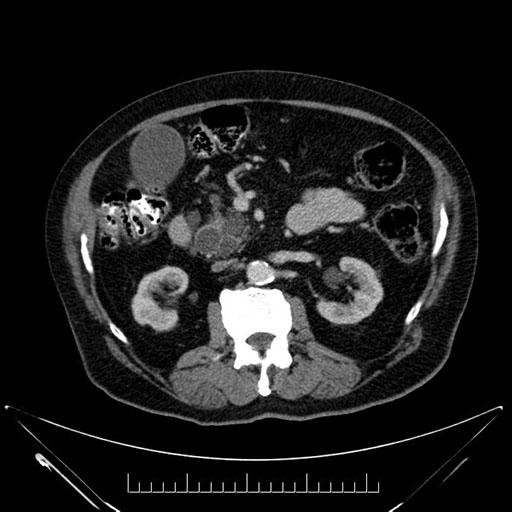

Whipple (pancreaticoduodenectomy) [case 7]

Axial - stented

Based on your CT findings, which issue(s) would give reason for "planned slowing down moment(s)" in this case?

Considering a standard Whipple procedure, what step(s) of the operation would you do differently in this case?